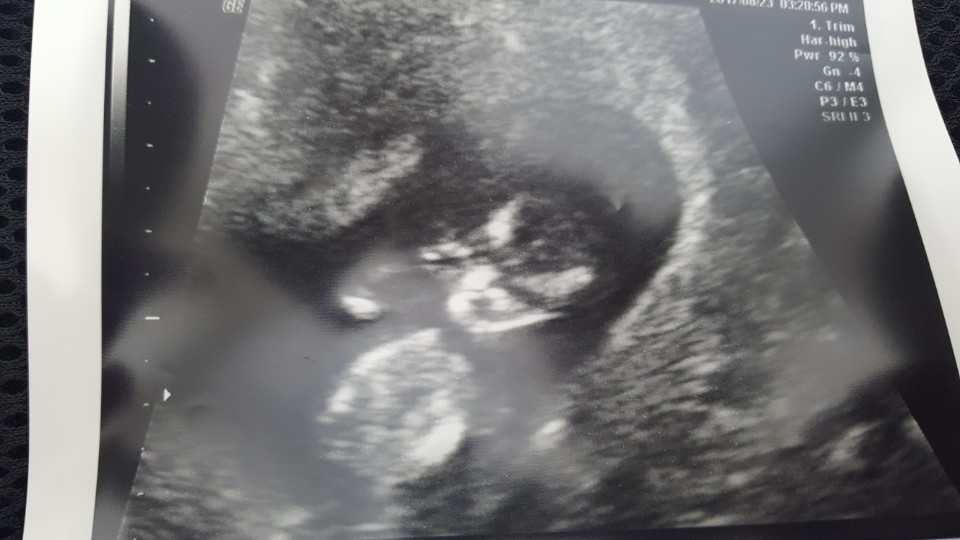

아내 몸속에 우리가 빚은 생명체를 확인한 2017년 6월 16일 금요일.

성별을 알기 전에는 조인성과 김태희 성별을 알고는 김태희를 상상했던 망고(태명), 태어난 다온이를 보고 알게 된 '유전의 힘은 강하다'